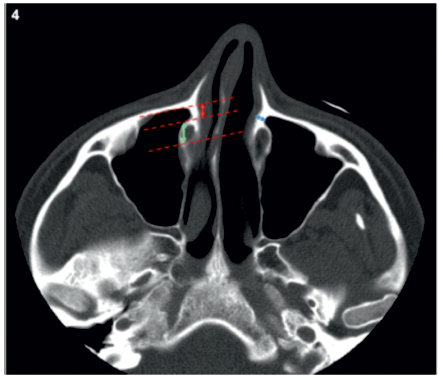

Para medir as larguras do RPL (largRPL) e do CNL (largCNL) foi traçada uma linha paralela à face posterior da parede anterior do seio maxilar e outras duas linhas paralelas a esta, uma tangente à parede anterior e outra à parede posterior do CNL, tendo sido medida a distância entre estas (Figura 4). Tendo em conta a sua largura, o RPL foi depois classificado de acordo com os critérios propostos por Simmen e colegas (14) em tipo I, caso esta fosse inferior a 3 mm, tipo II nos casos em que a largura estivesse compreendida entre 3 e 7 mm e tipo 3 caso esta fosse superior a 7 mm.

Foi também medida a espessura da parede medial do RPL (espRPL) (Figura 4).

Figura 4 Exemplo da metodologia utilizada para avaliar a largura do recesso pré-lacrimal (seta vermelha) e do canal nasolacrimal (seta verde) e a espessura da parede medial do recesso pré-lacrimal (seta azul).